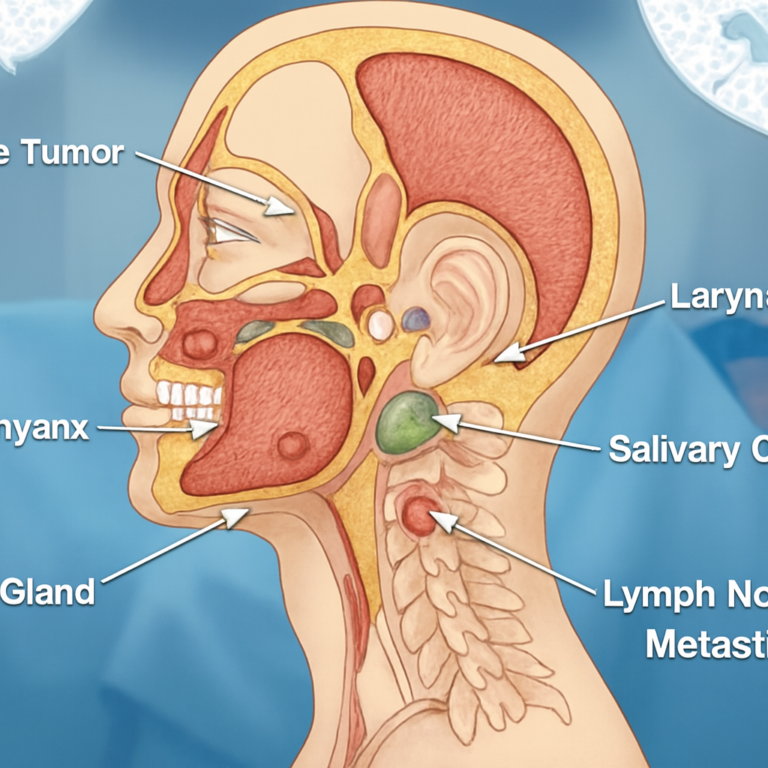

Opening the Door to Discovery Oral cancer is a life‑altering disease that affects thousands of patients every year. It begins in the…

Prolegomenon Head and Neck cancers specialist in Mira Road. Head and Neck cancers are among the most complex and challenging forms of…

What This Article Offers If you or your loved one has been diagnosed with oral cancer, you’re probably feeling scared, confused, or…